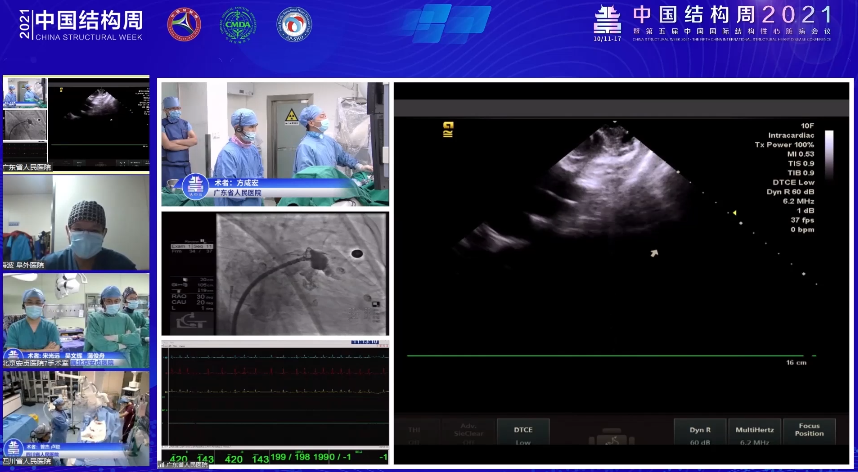

会议伊始,复旦大学附属中山医院的周达新教授张晓春教授团队以手术直播的方式给我们带来梳状肌发达、左心耳远端开口过大的房颤患者行左心耳封堵手术一例。在术中,团队凭借高超的手术技术和丰富的临床经验,及时更换封堵器类型成功完成手术,充分显示了在面对突发情况下,术者沉着冷静的操控能力,或将成为临床医师新的参考范本;随后,广东省人民医院方咸宏教授团队则在ICE指导下,使用WATCHMAN封堵器完美呈现了一场单纯左心耳封堵手术,并指出,ICE由于其能够实现心脏结构的实时可视化以及不需全身麻醉的特点,在未来或可取代食道超声;陆军军医大学附属第一医院宋治远教授团队紧随其后,带来一例比较罕见的主动脉缩窄病例,并介绍了一款本中心自主研发的手术直播机器人系统,获得各位与会专家的点赞无数;山东千佛山医院闫素华教授胡和生教授团队则完美呈现一场消融联合左心耳封堵一站式手术,就如何为梳妆肌发达患者选择封堵器尺寸这一话题进行了讨论,探讨了穿刺位点对轴向的影响,其规范化的手术流程颇具教育意义;最后,西安交通大学第一附属医院张玉顺教授则以病例讲解的方式分享单纯左心耳封堵术一例,充分展示出封堵器尺寸和植入深度对LAAC的重要性。